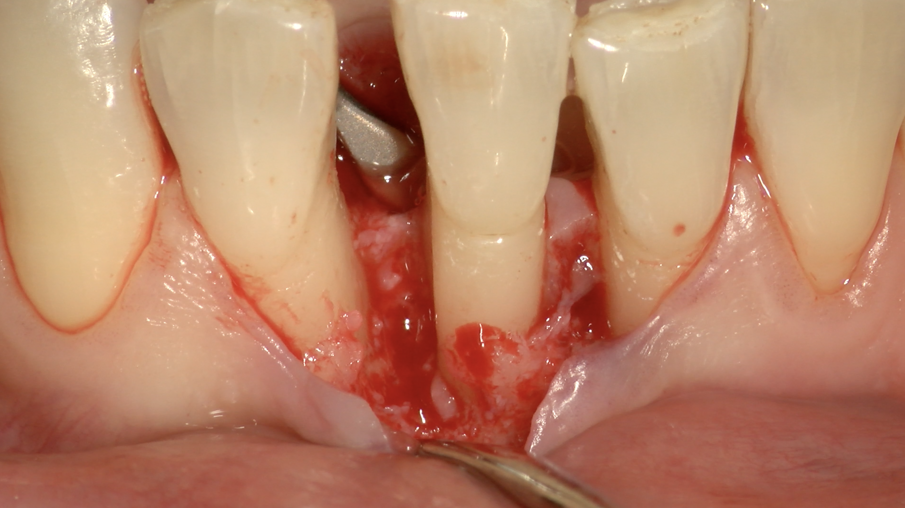

Il Paziente veniva premedicato con Zitromax 500 mg e Ibuprofene 400 mg. Eseguita anestesia loco regionale con articaina 1:100.000 con adrenalina veniva sollevato un lembo muco periosteo a spessore totale con tecnica di preservazione di papilla MPPT (Cortellin i 1995) e incisione intrasulculare (Figg 6d, 6e). Il difetto in sede interprossimale e vestibolare è stato degranulato con ultrasuoni e curette manuale. Raggiunta la perfetta decontaminazione del sito è stata preparata la barriera GUIDOR matrix barrier partendo dalla configurazione specifica per difetti interprossimali (DC double curved) in modo da renderne corretta la dimensione mesio distale e apico coronale (Fig. 6f) .

Il lembo stesso è stato suturato con un punto a materassaio verticale in e-PTFE e con punti singoli in Prolene 7.0 a livello delle due papille distale e mesiale (Fig. 6g).

Fig. 6d - Lembo sollevato con preservazione papille.

Fig. 6e - Difetto infraosseo mesiale.

Fig. 6f - Membraba Guidor in situ.

Fig. 6g - Lembo suturato.